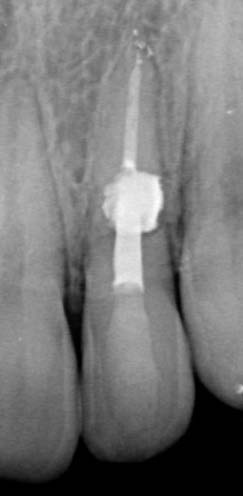

The patient started orthodontic treatment, however, tooth 2.2 was temporarily not included in the orthodontic therapy at the endodontist's request, who was willing to observe it for a year. Furthermore, increased resorption could have been provoked. As of today, the tooth is included in the orthodontic treatment and is being followed up.

In eighteen-month time, the stabilized process is observed, meaning that the diagnosis has been correct and the manual work has been performed without problems. No complaints are observed.